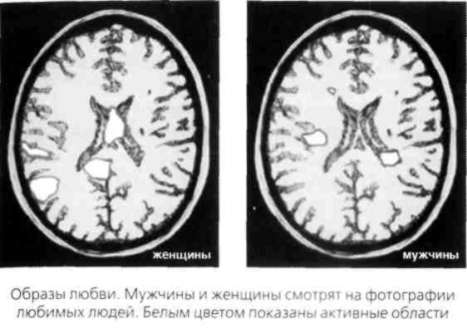

ГЕОГРАФИЯ СЕКСА И ЛЮБВИ В 2005 году доктор Люси Браун, профессор медицинского колледжа Альберта Эйнштейна в Нью-Йорке, вместе с самым известным биоантропологом мира, Хелен Фишер из Университета Рутджерса, провели исследование результатов сканирования мозга 1 7 молодых мужчин и женщин. Эти люди только что вступили в новые отношения и называли себя «безумно влюбленными», то есть они переживали период страсти или начала романтической любви. Сканирование мозга позволило физиологически объяснить, почему во время влюбленности мы ощущаем себя определенным образом — почему любовь является столь сильным чувством и почему отказ вызывает настолько болезненную и мучительную реакцию. Ученые изучали участок мозга, отвечающий за пристрастия, память, эмоции и внимание, который называется «хвостатым ядром», а также вентрально-тегментальную область — ту часть мозга, откуда допамин поступает в другие участки. Эти области явно выделялись на снимках мозга, когда испытуемым показывали фотографии их любимых. Ученые также сравнили данные сканирования с исследованиями эректильной реакции мужчин на фотографии женщин. Они проанализировали данные, полученные при исследовании пар, которые долгое время были вместе (и людей, и животных). Ученые обнаружили, что в начале периода влюбленности вентрально-тегментальная область выбрасывает допамин в хвостатое ядро. Затем хвостатое ядро посылает сигналы с требованием большего количества допамина. Чем больше допамина вырабатывает ваш мозг, тем счастливее вы себя чувствуете. Фишер и Браун также подтвердили, что «безумная любовь» вызывает ощущения, сходные с наркотическим опьянением, что объясняется гормональной активностью. ![]() Фишер и Браун установили, что с романтической любовью в головном мозге связано именно хвостатое ядро. Они обнаружили, что длительная привязанность концентрируется во фронтальной части и основании мозга, в вентральной скорлупе и бледном ядре. Чувства, связанные со страстью и сексуальным возбуждением, воздействуют на другие области, преимущественно расположенные в левом полушарии мозга. Это очень важное исследование снимает покров тайны с любви и позволяет нам относиться к этому чувству более объективно. Любовь — это химический коктейль из гормонов счастья. Тех, кто впал в зависимость от этого коктейля, вполне можно назвать «наркоманами любви». ПОЧЕМУ МУЖЧИНЫ И ЖЕНЩИНЫ ВОСПРИНИМАЮТ ЛЮБОВЬ ПО-РАЗНОМУ Фишер и Браун, вместе и по отдельности, проанализировали результаты сканирования мозга более 3000 «безумно влюбленных» студентов, полученные в тот момент, когда им показывали фотографии любимых. Ученые обнаружили, что у женщин, принимавших участие в исследовании, проявлялась повышенная активность хвостатого ядра (мы уже говорили, что область мозга, связанная с памятью, эмоциями и вниманием, «центр удовольствий», — это задняя теменная кора, которая участвует в формировании ментальных образов и воспоминаний). Мужчины, участвовавшие в исследовании, демонстрировали повышенную активность визуального участка коры и зон, связанных с обработкой зрительных образов, в том числе и той области, которая отвечает за сексуальное возбуждение. Бартельс и Зеки пришли к тому же выводу независимо. Приведенные ниже результаты сканирования мозга го иллюстрируют исследование, проведенное доктором Браун. Они показывают, в каком участке мозга «располагается» любовь и почему мужчины и женщины относятся к этому чувству по-разному. Это снимки мозга | мужчин и женщин, которые смотрят на фотографии людей, в которых они страстно влюблены. ![]() Вы видите, что у мужчин светлых участков меньше, чем у женщин. Однако, когда эти снимки показываются в цвете, становится ясно, что активизированные участки мужского мозга действуют более интенсивно. Обширные активизированные участки женского мозга гораздо менее активны. У женщин таких участков больше, и расположены они не там, где у мужчин. Это объясняет, почему мужчины и женщины относятся к любовным отношениям по-разному. В ходе другого исследования людям показывали эротические фотографии и одновременно проводили сканирование мозга. Браун и Фишер не обнаружили на снимках ни одного участка, связанного с «влюбленностью». Как уже отмечалось раньше, они выявили активность гипоталамуса, который управляет такими чувствами, как голод и жажда, а также мозжечковой миндалины, ответственной за возбуждение. Отсюда можно сделать вывод о том, что влюбленность и страсть — это разные состояния, поскольку в мозгу задействуются разные системы. В заключение скажем, что ученые доказали: при оценке представителей противоположного пола на ранней стадии любви в мозгу мужчин и женщин происходят совершенно разные процессы. У мужчин главное орудие оценки сексуального потенциала женщин — глаза. Женщины же оценивают потенциал мужчины в качестве долгосрочного партнера, опираясь на память. Страсть и любовь воздействуют на разные участки мозга. Это вовсе не одно и то же. КАК МУЖСКОЙ МОЗГ ОЦЕНИВАЕТ ПРИВЛЕКАТЕЛЬНОСТЬ ЖЕНЩИНЫ Когда Бартельс и Зеки показывали мужчинам фотографии привлекательных женщин, испытуемые демонстрировали повышенную активность двух участков мозга: отвечающего за визуальные образы и связанного с пенильной эрекцией (ну надо же, кто бы мог подумать!). Большинство мужчин любит глазами. Они постоянно смотрят на женщин, фантазируют о них и любят смотреть порно. И это не сюрприз для большинства из нас. Ученые выяснили, что когда в мужском мозгу активизируются эти участки, то те зоны, которые отвечают за моральные оценки, в буквальном смысле слова «засыпают». Трехлетний мальчик в душе изучает свои яички. «Мама, — спрашивает он, — это мои мозги?» «Пока нет», — отвечает мать. Визуальная мозговая сеть мужчины развивалась на протяжении миллиона лет. Мужчине нужно было смотреть на женщину, чтобы оценить ее способность произвести на свет здоровое потомство и обеспечить продолжение рода. Если женщина была молода и здорова, мужчина сразу же возбуждался и начинал процесс ухаживания. Вот почему мужчины влюбляются быстрее женщин — они более визуально мотивированы, а визуальные рецепторы мгновенны и очень быстро посылают в мозг сигнал, который активизирует выброс гормонов. Это также объясняет и то, почему мужчины более склонны к любви с первого взгляда. Мужчина использует глаза в первую очередь для оценки потенциала женщины. Когда мужчина заводится, происходит выброс гормонов и, как следствие, эрекция. Эти гормоны могут подавить способность к рациональному мышлению, в результате чего мужчины могут спонтанно принять решения, абсолютно не отвечающие их интересам. В такой ситуации эрекция подавляет рассудок. Подобный вывод вряд ли удивит женщину, имеющую опыт общения с мужчинами. Сканирование мозга, проведенное Дэвидом Бассом, показывает, что подобное поведение является универсальным, межкультурным явлением. |